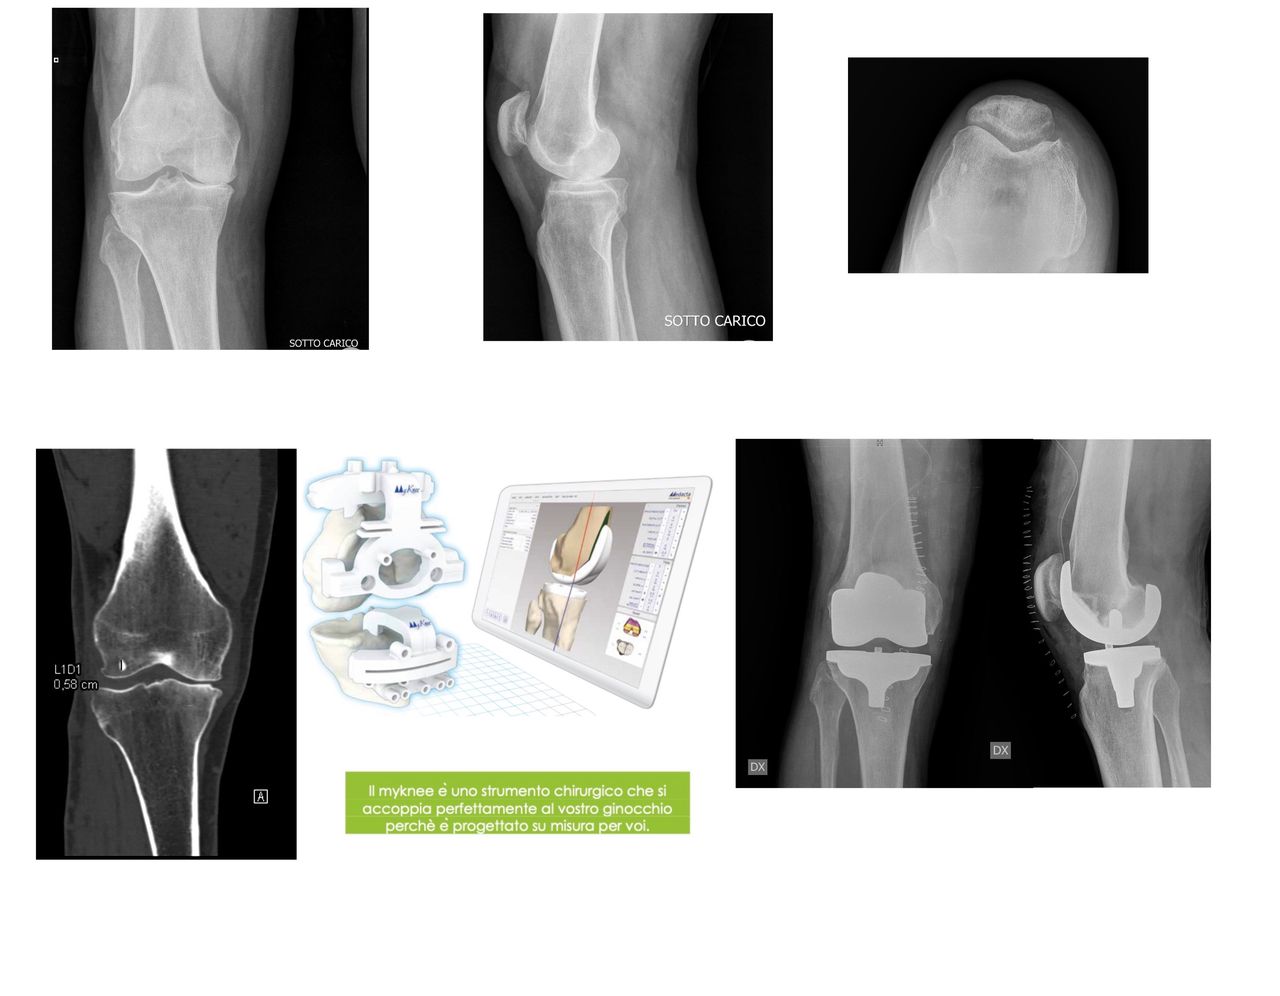

• Chirurgia protesica mini-invasiva di anca e ginocchio a Firenze – interventi eseguiti con approcci che riducono il trauma chirurgico, rispettano i tessuti e favoriscono un recupero più rapido.

• Planning pre-operatorio 2D e 3D – pianificazione computerizzata che assicura la massima precisione nella ricostruzione della biomeccanica articolare.